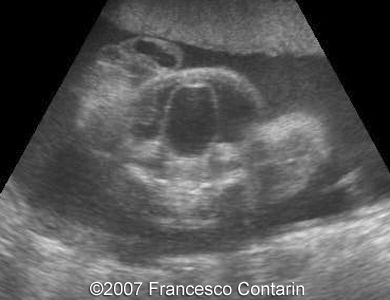

This is a 22-year-old woman (G4, P2) with unremarkable familiar history, referred to our hospital at 29 weeks of gestation due to a fetal ascites. There were no signs of maternal-fetal blood incompatibility. The ultrasound investigation revealed rhizomelia, postaxial polydactyly, small thorax, short ribs, ascites, increased abdominal biometric parameters, polyhydramnios. We supposed two diagnoses: Short rib-polydactyly syndrome versus Jeune syndrome (asphyxiating thoracic dystrophy).

Images 1, 2. 29th week of pregnancy -  shortened femur (left); and ulna (right).

1

2